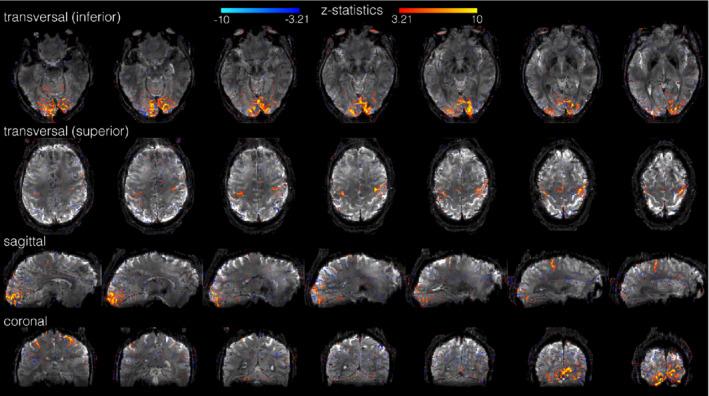

An improved, completely self-navigated version of the TURBINE sampling scheme was designed for fMRI at 7 Telsa. To demonstrate the image quality and spatial specificity of the acquisition, thin-slab visual and motor BOLD fMRI at 0.67 mm isotropic resolution (16 mm slab, TRvol = 2.32 s), and 0.8 × 0.8 × 2.0 mm (whole-brain, TRvol = 2.4 s) data were acquired. To prioritize the high spatial fidelity, we employed a temporally regularized reconstruction to improve sensitivity without any spatial bias.

RESULTS

TURBINE images provide high structural fidelity with almost no distortion, dropout, or T * blurring for the thin-slab acquisitions compared to conventional 3D EPI owing to the radial sampling in-plane and the short echo train used. This results in activation that can be localized to pre- and postcentral gyri in a motor task, for example, with excellent correspondence to brain structure measured by a T -MPRAGE. The benefits of TURBINE (low distortion, dropout, blurring) are reduced for the whole-brain acquisition due to the longer EPI train. We demonstrate robust BOLD activation at 0.67 mm isotropic resolution (thin-slab) and also anisotropic 0.8 × 0.8 × 2.0 mm (whole-brain) acquisitions.

方法

为在 7T 下进行 fMRI,设计了一种改进的、完全自我导航的 TURBINE 采样方案。为了展示采集的图像质量和空间特异性,我们在 0.67 毫米各向同性分辨率(16 毫米片层,TRvol = 2.32 秒)下进行了薄切片视觉和运动 BOLD fMRI,以及 0.8×0.8×2.0 毫米(全脑,TRvol = 2.4 秒)数据采集。为了优先考虑高空间保真度,我们采用了时间正则化重建来提高灵敏度,而没有任何空间偏差。

结果

与传统的 3D EPI 相比,TURBINE 图像提供了几乎没有失真、缺失或 T * 模糊的高结构保真度,这是由于在平面内进行的径向采样和使用的短回波链。这导致例如在运动任务中,可以将激活定位到中央前回和中央后回,与 T -MPRAGE 测量的大脑结构具有极好的对应关系。由于 EPI 链较长,TURBINE(低失真、缺失、模糊)的优势对于全脑采集会降低。我们在 0.67 毫米各向同性分辨率(薄片)下证明了稳健的 BOLD 激活,并且还在各向异性 0.8×0.8×2.0 毫米(全脑)采集下证明了稳健的 BOLD 激活。